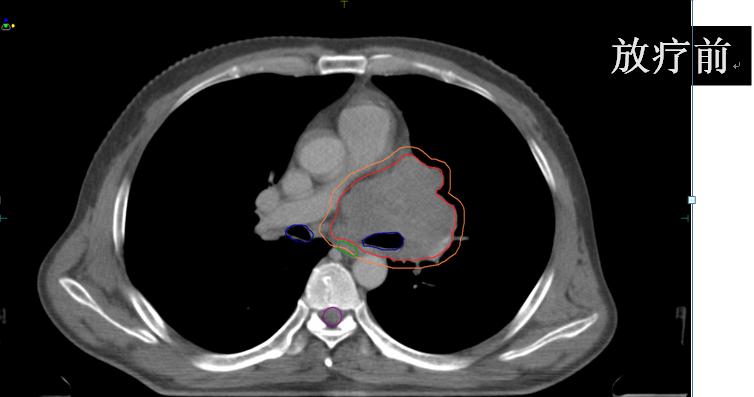

男性,48岁,2016年4月无明显诱因出现左肩背部疼痛,自服布洛芬可缓解,其后疼痛逐步加重伴咳嗽、咳痰,偶有痰中带血,自服镇咳药物及抗生素效果欠佳,2017年2月初诊胸部CT:左肺上叶肺门旁占位合并远端阻塞性不张及炎症,纵隔淋巴结肿大。气管镜活检病理:小细胞肺癌。骨扫描未见异常,头颅CT未见异常。遂于外院行EP方案化疗,期间出现恶心、呕吐、脱发、白细胞下降,对症支持治疗后好转;2周期化疗后咳嗽、咳痰减轻,左肩背部静息时疼痛及痰中带血消失;但出现胸闷、气短、声音嘶哑,咳嗽时仍有右胸剧痛,休息后缓解。复查胸部CT:左肺上叶支气管变窄并软组织肿块形成,符合中央型肺癌改变,伴纵隔、左肺门及左侧锁骨上淋巴结转移;右肺上叶结节,性质待定,双肺轻度间质性改变。综合评价:病情进展;考虑化疗效果欠佳,建议行放疗。

患者急诊来我院,具体治疗计划如下:

• (肺及纵隔病灶)iGTV1/GTV1/CTV1/70Gy/60Gy/50Gy/20F;

• (锁骨上病灶)GTV2/CTV2/60Gy/50Gy/20F。